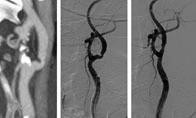

La stenosi carotidea è una patologia che comporta il restringimento delle arterie carotidi, principali vie di afflusso del sangue al cervello. Questa condizione, che colpisce prevalentemente persone oltre i 65 anni, riduce il flusso sanguigno, limitando l’apporto di ossigeno e nutrienti essenziali al cervello.